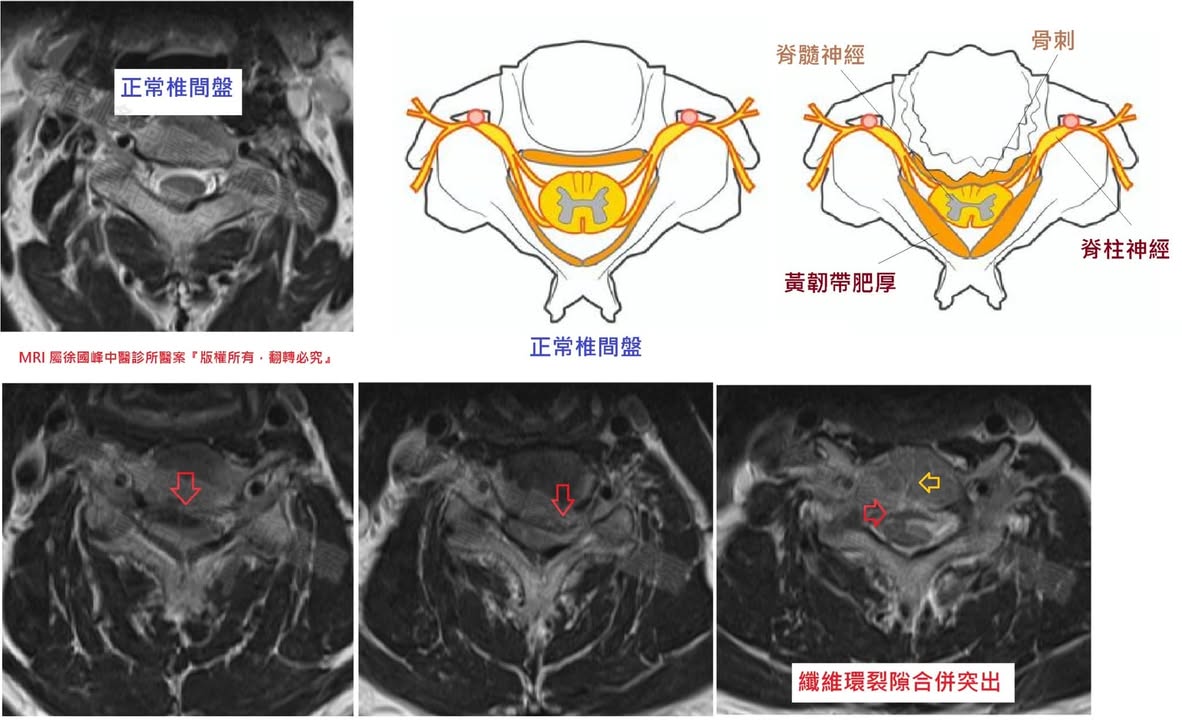

⭕️脊髓病變原因:

目前科學界朝向頸椎間盤退變為主,也就是我們說的骨刺,當年齡增長後,椎間盤會變扁,並開始膨脹。而且含水量會下降,開始變乾,然後就變得更硬化。此問題會導致椎間盤縮小或崩塌、椎間盤空間和高度變小。因為椎間盤變矮變扁,脊椎骨靠得更近。脊椎體因為旁邊椎間盤的崩塌,會長出多餘的骨頭(骨刺),以強化脊椎骨結構。這些骨刺會造成脊柱的硬化。他們也會造成脊髓腔變窄小,壓迫和推擠脊髓。